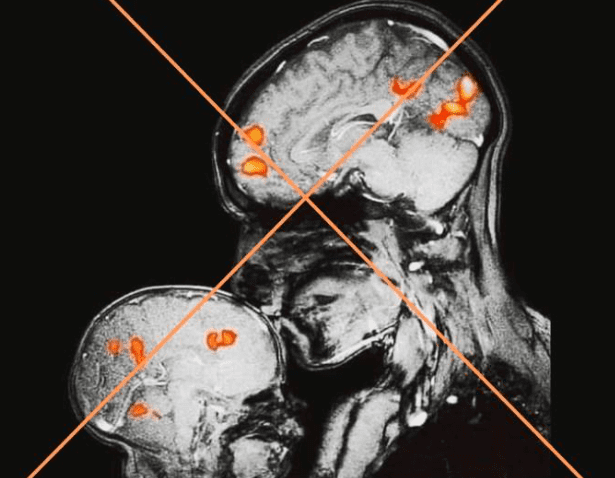

Besar activa zonas del cerebro relacionadas con el placer

Especialistas señalan que besar estimula regiones cerebrales vinculadas con emociones positivas, lo que contribuye a generar bienestar y reforzar la conexión emocional entre las personas.